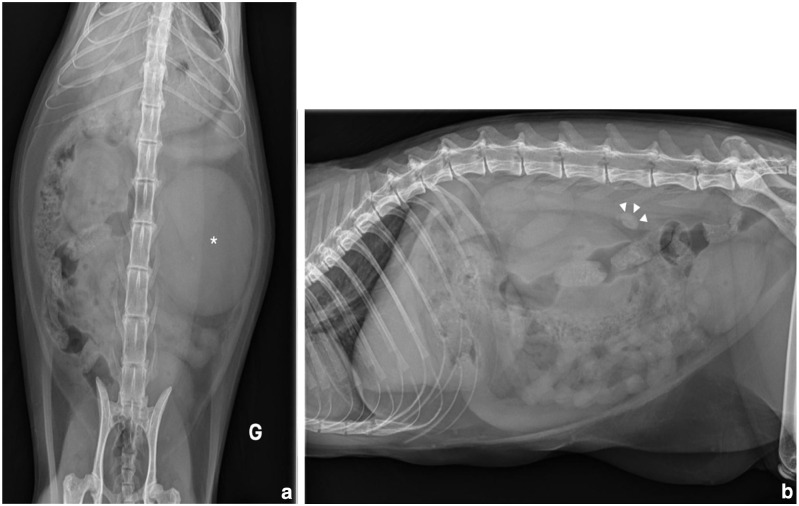

病例总结:一只2岁雌性绝育家短毛猫,有1周嗜睡和吞咽困难的病史,被送到兽医教学医院。体格检查发现严重的左肾肿大,高热和腹痛。腹部超声显示左侧输尿管因输尿管结石阻塞而扩张,并伴有明显的囊下积液。尿液分析显示尿液呈碱性,有鸟粪石结晶。肾盂及膀胱尿液培养假中葡萄球菌阳性。怀疑因存在产脂细菌而感染鸟粪石输尿管结石。通过输尿管切开术取出输尿管结石,并顺行放置临时输尿管支架。红外光谱结果显示为纯鸟粪石尿石症。手术后35天通过膀胱镜取出支架。在6个月的随访中,这只猫仍然表现良好。相关性和新信息:据作者所知,这是猫因肾盂肾炎导致鸟粪石输尿管结石的第一例。

Case summary: A 2-year-old female spayed domestic shorthair cat with a 1-week history of lethargy and dysorexia was presented to a veterinary teaching hospital. Physical examination identified severe left nephromegaly, hyperthermia and abdominal pain. Abdominal ultrasound revealed a left ureteral dilation due to obstruction by a ureterolith, associated with marked subcapsular effusion. Urinalysis showed alkaline urine with crystals of struvite. Culture of urine from the renal pelvis and the urinary bladder was positive for Staphylococcus pseudintermedius. An infected struvite ureterolith due to the presence of urease-producing bacteria was suspected. The ureterolith was removed via ureterotomy and a temporary ureteral stent was positioned in an antegrade fashion. Results of infrared spectroscopy showed pure struvite urolithiasis. The stent was removed via cystoscopy 35 days after surgery. The cat was still doing well at the 6-month follow-up.